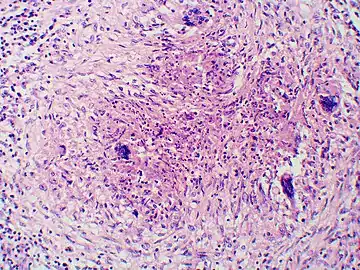

Once suspected, the diagnosis of blastomycosis can usually be confirmed by demonstration of the characteristic broad based budding organisms in sputum or tissues by KOH prep, cytology, or histology.[27] Tissue biopsy of skin or other organs may be required in order to diagnose extra-pulmonary disease. Blastomycosis is histologically associated with granulomatous nodules.

- Granuloma with early suppuration. Fungal organisms difficult to recognize at this low magnification.